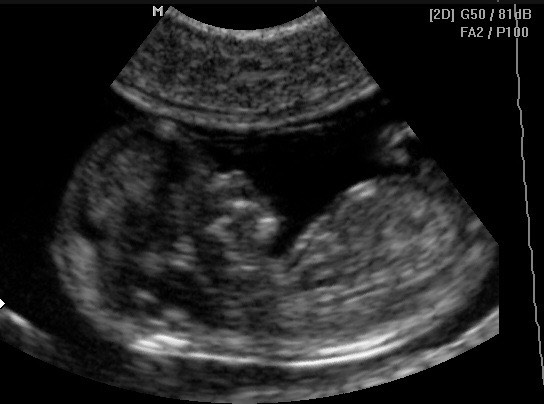

Добрый вечер! Девочки, сегодня расскажу про скрининг на 10-14, 20-24, 30-32. Лучше скрининг делать в середине этих недель, но опять же только ваш личный врач должен назначить лучший промежуток! ТК это очень важное исследование, его ни в коем случае пропускать нельзя и затягивать тоже! В эти три важные даты беременности будут смотреть параметры вашего ребёночка! Советую делать скрининг там, где вам могут записать его на диск, ТК на фотографиях не всегда видны все нюансы, а вот диск всегда можно показать врачу и многие вопросы могут отпасть! Меня в моей консультации отправляли к Лебедеву, это жутко дорогой врач и говорят очень хороший, но 7000 отдать за узи это не серьёзно, правда! Поэтому в нашем городе есть не менее профессиональные и компетентные врачи, которые смогут вам сделать качественный скрининг! Почему это важно, расскажу! У меня у детей проблема, у одного и второго расширены желудочки, когда данный диагноз поставили нам с первым ребёнком это была для меня трагедия! Я оставила столько денег и нервов бегая по всевозможным врачам, что даже не передать! Почему-то с первым ребёнком меня никто из врачей не просил принести и показать свои скрининги и показать, как обстояло дело внутриутробно, а это очень важно, ТК получено это внутриутробно или уже после родов это существенно!

И по поводу страхов делать УЗИ, я в первую беременность делала узи почти раз в две недели, мне было так спокойнее, когда я видела, что малышу хорошо, он дышит, дёргает ручками и ночками! Ничего вредного в этом нет, вы не облучаете своего ребёночка, сейчас такая техника, что все безопасно, тч если очень хочется посмотреть и проверить, лучше сходить, чем ночь не спать, думать, переживать! )))) если есть вопросы, не стесняйтесь, задавайте!)))